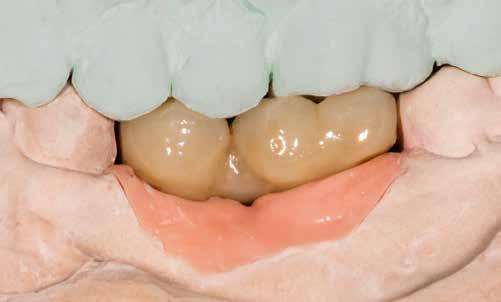

1–2. képek: Kiindulási helyzet.

3. kép: Új teleszkópos fogpótlás az 16, 15, 13, 23 és 27 fogakra.

Kiindulási helyzet

A páciens látlelete a következő:

• krónikus általános parodontitis

• a 24-től terjedő parodontális fekély

• hatástalan kapcsos felső fogpótlás (1-2. képek)